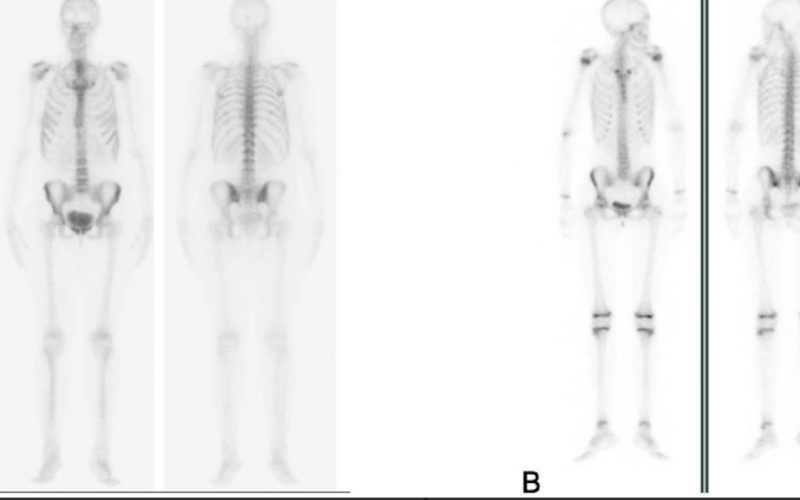

Una gammagrafía ósea es una prueba de diagnóstico por imágenes de medicina nuclear que ayuda a diagnosticar y controlar varios tipos de enfermedades óseas. El médico puede solicitarte una gammagrafía ósea si tienes dolor óseo inexplicable, una infección ósea o una lesión ósea que no puede verse en una radiografía estándar.

Una gammagrafía ósea también puede ser una herramienta importante para detectar el cáncer que se ha esparcido (metastatizado) al hueso desde la ubicación original del tumor, como la mama o la próstata.

Una gammagrafía ósea implica inyectar una cantidad muy pequeña de material radiactivo (marcador) dentro de una vena. La sustancia viaja a través de la sangre hasta los huesos y órganos. A medida que esta va desapareciendo, emite un poco de radiación. Esta es detectada por una cámara que lentamente escanea el cuerpo.

Toma imágenes del marcador que hay en sus huesos. El técnico puede solicitarle que cambie de posición durante el procedimiento. Esto ayuda a obtener imágenes desde diferentes ángulos. Una gammagrafía ósea de todo el cuerpo tarda aproximadamente 1 hora en completarse.

La cámara gamma detecta las emisiones de energía de la radiosonda en su cuerpo y las convierte en una imágen. La cámara gamma de por sí no emite ninguna radiación. Tiene detectores de radiación denominados cabezas de cámara gamma.